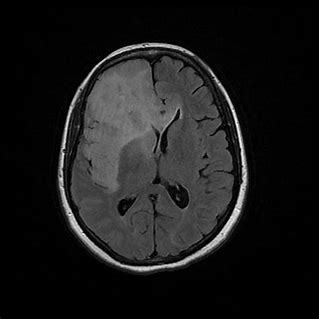

Q

White matter abnormality

Bilateral

frontal and temporal lobes

internal capsule

A

1. Gliomatosis cerbri

2. encephalitis

3. ADEM